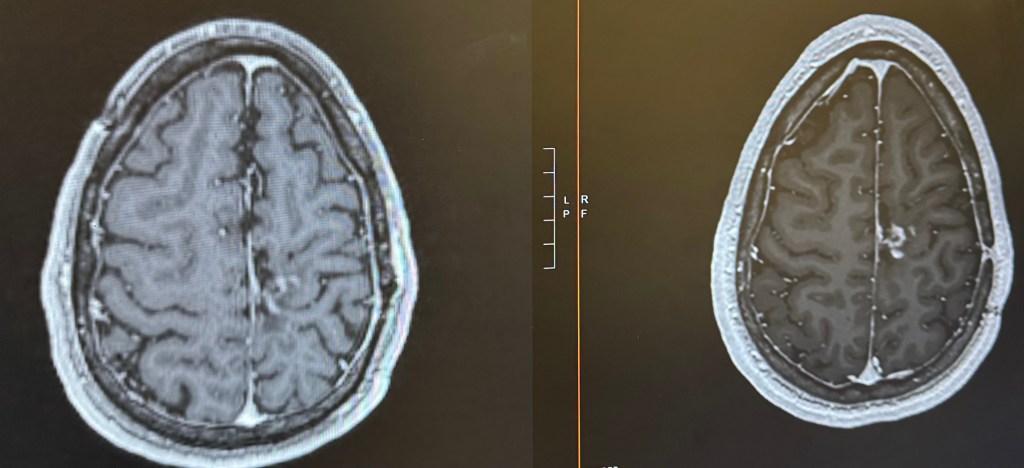

(right side is an older scan, left side is a recent scan. The white area just to the right of the midline is the tumor)

It was truly hard to believe. In the past, I would be immediately hesitant to fully accept the good news because experience has conditioned me to expect the other shoe to drop. However, one of the many things my partner, Chris, has taught me is to lean into the good news. So, I celebrated!

The next scan showed slightly further decrease in size, and my most recent scan showed stability if not further decrease. I have my next scan this Tuesday (March 17th), which I hope continues the good news. Leading up to the MRIs, I will always get scanxiety about when this ends up being too good to be true, but in between those scans I continue planning to live life fully.